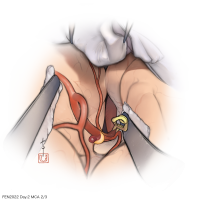

FEN2022シリーズ